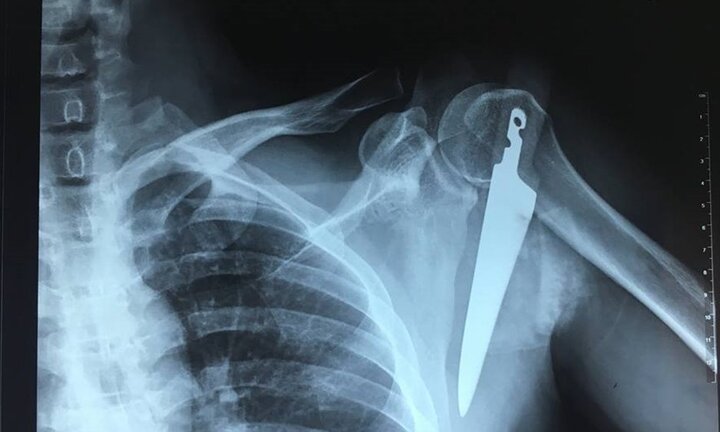

Người đàn ông bị dao dài 20cm đâm vào vai do vô tình vấp ngã trong bếp

Con dao găm đâm sâu vào vùng vai trái, ngay dưới xương đòn của người đàn ông, chảy rất nhiều máu.